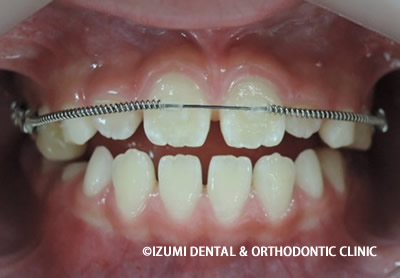

上顎から矯正装置を装着していきます。

上顎の歯が揃ってから、下額に矯正装置(ブラケット)を装着します。

終了時(1年6ヶ月)